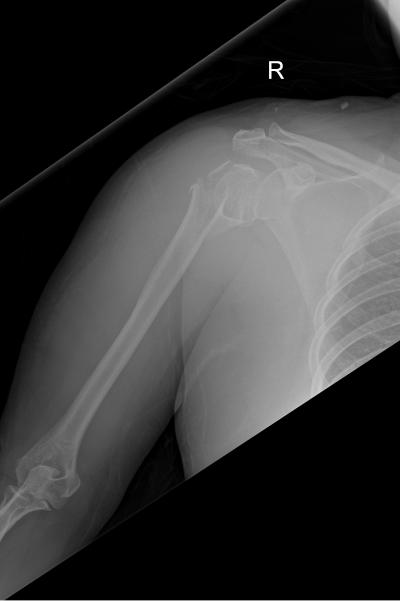

Figure 1: Anteroposterior radiograph of right shoulder: displaced fracture neck of right humerus.